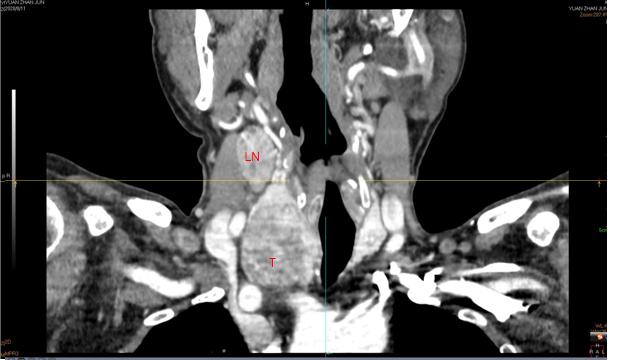

专科检查:气管居中,双侧颈动脉搏动正常,颈静脉无怒张,肝颈静脉回流征阴性。右侧甲状腺区可触及肿物,大小约4*4cm,质中,表面光滑,无压痛,随吞咽活动,表面皮肤正常,肿物与皮肤无粘连。左侧甲状腺区及峡部未触及明显肿物。右颈部Ⅲ、Ⅳ区可触及肿大淋巴结,较大者大小约3*2cm,质中,表面光滑,无压痛,活动。左侧颈部未触及异常肿大淋巴结。

二、下一步?评估病变范围

- 电子计算机断层成像(CT)